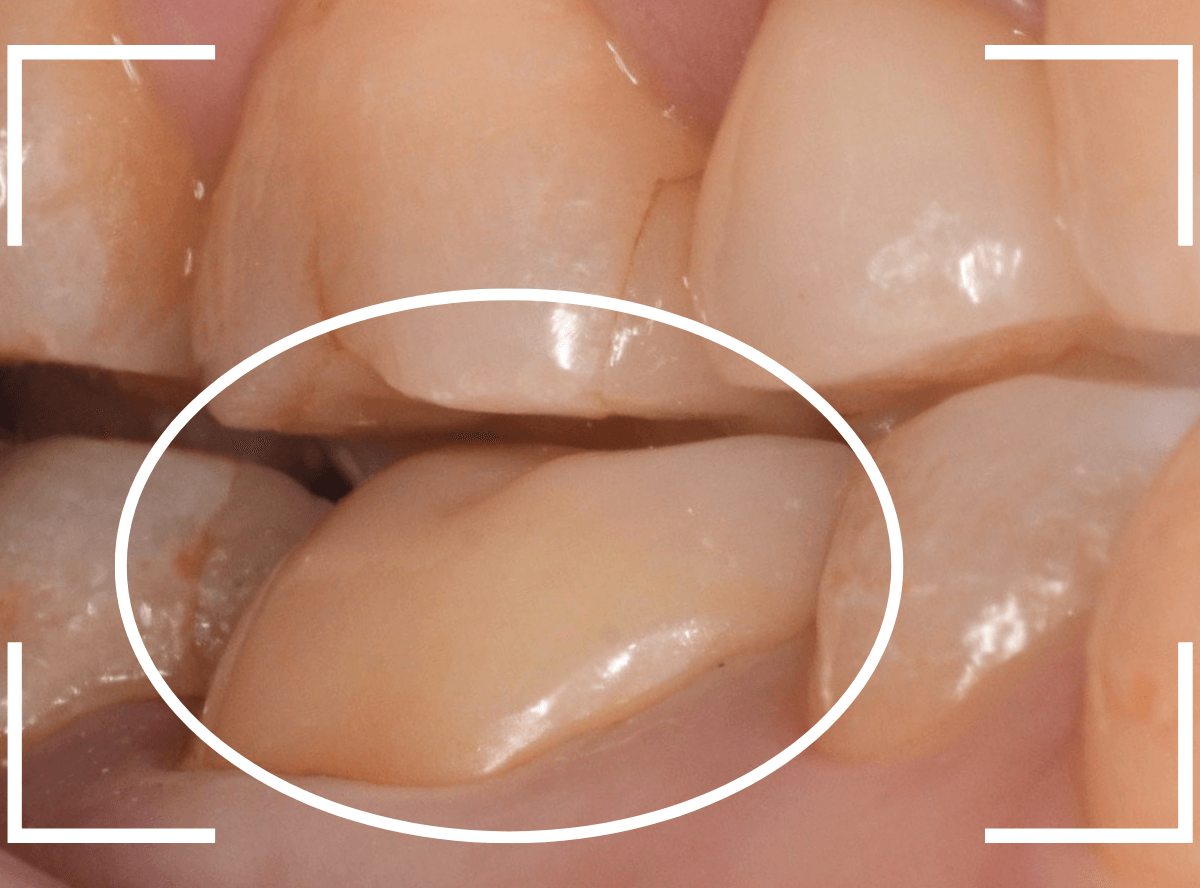

さし歯を入れるスペースがない!

一番奥の歯が土台(コア)の治療までで中断してしまってる患者さんの例です。

本来であれば、この上にさし歯を作らなければいけないのですが、この時点でかみ合ってしまい、さし歯を作ろうにも作りづらい状況でうやむやのうちに治療中断になってしまったようです。

まず、土台の治療をしてから時間が経過していることと、不適合になっている事から、外して中を調べます。

すると、土台の中で虫歯にもなっていました。

(〇部の赤い部分)

こういった事は、レントゲン写真でもよくわからない事が多く、土台を外す治療は本当に神経を使います。